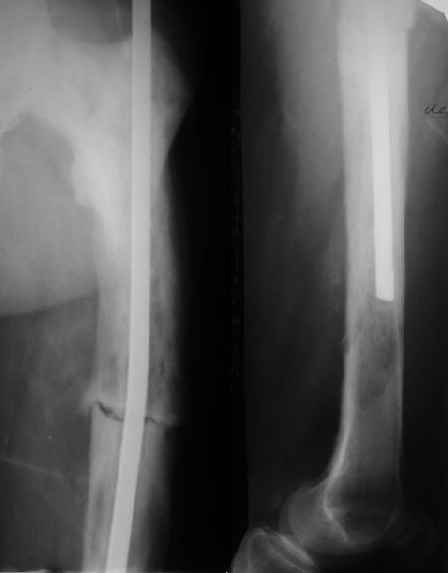

Пациент 82 лет, поступил через 5 мес. с несросшимся переломом после

открытого интрамедуллярного остеосинтеза. Выполнили реостеосинтез

стержнем 12 мм. ( мах. доступного нам в 2003 г.) Через 4 мес

динамизация. В течении 2х лет сращения нет, тем не менее конечность

опорна (ходит с тростью). От очередного реостеосинтеза отказались из-за

сопутств. патологии.